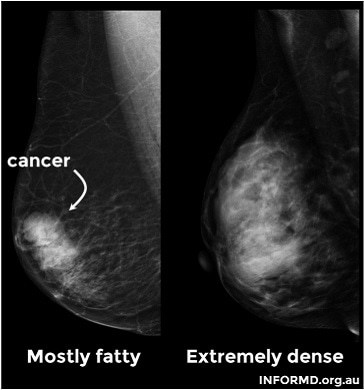

Know the facts, bust myths and keep yourself informed about breast density and its impacts on your health